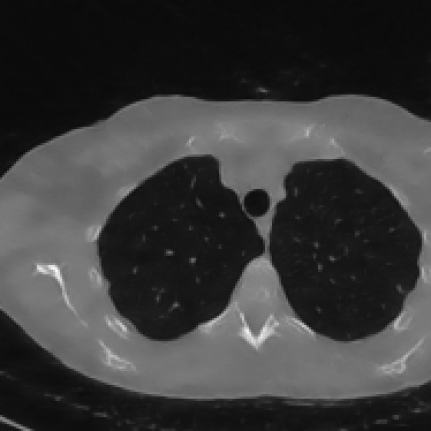

2.1 Experiments on a synthetic image

To analyze the behavior of the proposed weighting scheme for different choices of 𝒙~~𝒙\tilde{\boldsymbol{x}}over~ start_ARG bold_italic_x end_ARG, we conduct a simple experiment involving sparse CT reconstruction using a synthetic image, shown as the first image in Figure 3. We denote as 𝒙GTsuperscript𝒙𝐺𝑇\boldsymbol{x}^{GT}bold_italic_x start_POSTSUPERSCRIPT italic_G italic_T end_POSTSUPERSCRIPT this synthetic ground truth which incorporates structures commonly encountered in tomographic imaging: homogeneous regions with regular shapes simulating tumoral masses, high-density areas representing bones or metallic implants, and objects with extremely thin edges.

The corrupted measurement 𝒚δsuperscript𝒚𝛿\boldsymbol{y}^{\delta}bold_italic_y start_POSTSUPERSCRIPT italic_δ end_POSTSUPERSCRIPT is then computed by simulating projections from the ground truth image 𝒙GTsuperscript𝒙𝐺𝑇\boldsymbol{x}^{GT}bold_italic_x start_POSTSUPERSCRIPT italic_G italic_T end_POSTSUPERSCRIPT, according to the image formation model in Equation (1.1) using a fan-beam scanning geometry with only 45 projections uniformly distributed over the angular range [0,180]0180[0,180][ 0 , 180 ]. The noise 𝒆𝒆\boldsymbol{e}bold_italic_e is obtained by sampling 𝒛𝒩(𝟎,𝑰)similar-to𝒛𝒩0𝑰\boldsymbol{z}\sim\mathcal{N}(\boldsymbol{0},\boldsymbol{I})bold_italic_z ∼ caligraphic_N ( bold_0 , bold_italic_I ) and computing:

We conducted two simulations with different noise intensity, setting ν=0.005𝜈0.005\nu=0.005italic_ν = 0.005 and ν=0.02𝜈0.02\nu=0.02italic_ν = 0.02. For all the experiments, we have chosen η=2105𝜂2superscript105\eta=2\cdot 10^{-5}italic_η = 2 ⋅ 10 start_POSTSUPERSCRIPT - 5 end_POSTSUPERSCRIPT. Regarding the regularization parameter λ𝜆\lambdaitalic_λ, we have assigned consistent heuristic values across all weighted methods. To validate the selections of the space-variant parameters, we compare the results obtained using the proposed adaptive weighted TV model (2.2) method with those derived from global TV regularization (1.3) (the value of the regularization parameter λ𝜆\lambdaitalic_λ has been adequately set ad hoc for the global TV). We briefly present the results of this simulation, which firstly demonstrate the effectiveness of the proposed weights and subsequently confirm that setting 𝒙~=𝒙GT~𝒙superscript𝒙𝐺𝑇\tilde{\boldsymbol{x}}=\boldsymbol{x}^{GT}over~ start_ARG bold_italic_x end_ARG = bold_italic_x start_POSTSUPERSCRIPT italic_G italic_T end_POSTSUPERSCRIPT yields a highly accurate reconstructed image.

These findings are further confirmed by Figure 3, which presents a cropped view of the restored images in the case ν=0.02𝜈0.02\nu=0.02italic_ν = 0.02. Clear differences in the outputs are noticeable, particularly in the reconstruction of finer cross details and contrast. Notably, the global TV method consistently fails to reconstruct the cross, regardless of the parameter settings. The superior reconstruction performance achieved when 𝒙~=𝒙GT~𝒙superscript𝒙𝐺𝑇\tilde{\boldsymbol{x}}={\boldsymbol{x}}^{GT}over~ start_ARG bold_italic_x end_ARG = bold_italic_x start_POSTSUPERSCRIPT italic_G italic_T end_POSTSUPERSCRIPT highlights the effectiveness of adapting regularization to image pixels when a highly accurate approximation of the target image is available. Figure 3 also includes the plot of the relative error, where the relative position of the curves is maintained across all iterations, consistently with the behavior discussed in Table 3. The plots clearly demonstrate that the error stabilizes, suggesting that a stationary point has been achieved for each method. We specify that the graphs display the executions carried out with 10000 iterations of the Chambolle-Pock method to analyze the behavior until convergence, whereas the images visually show no further changes after a few hundred iterations.

Figure 3: Results of the experiment on the synthetic image with higher noise (ν=0.02𝜈0.02\nu=0.02italic_ν = 0.02). In the first row, from left to right: the entire ground truth image with a red square depicting the crop of interest, cropped zooms on the reconstructions by GT-W1𝑊subscript1W\ell_{1}italic_W roman_ℓ start_POSTSUBSCRIPT 1 end_POSTSUBSCRIPT, FBP-W1𝑊subscript1W\ell_{1}italic_W roman_ℓ start_POSTSUBSCRIPT 1 end_POSTSUBSCRIPT, TV-W1𝑊subscript1W\ell_{1}italic_W roman_ℓ start_POSTSUBSCRIPT 1 end_POSTSUBSCRIPT and by the global TV model. In the second row: plot of the Relative Error over the iterations.